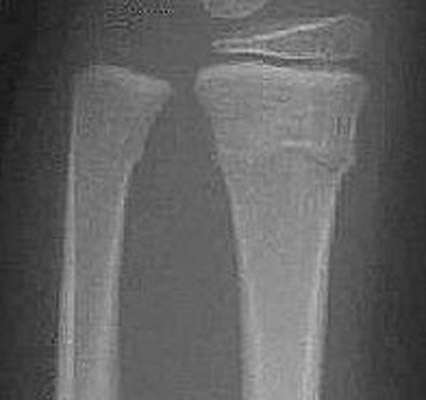

Return to Torus Fracture